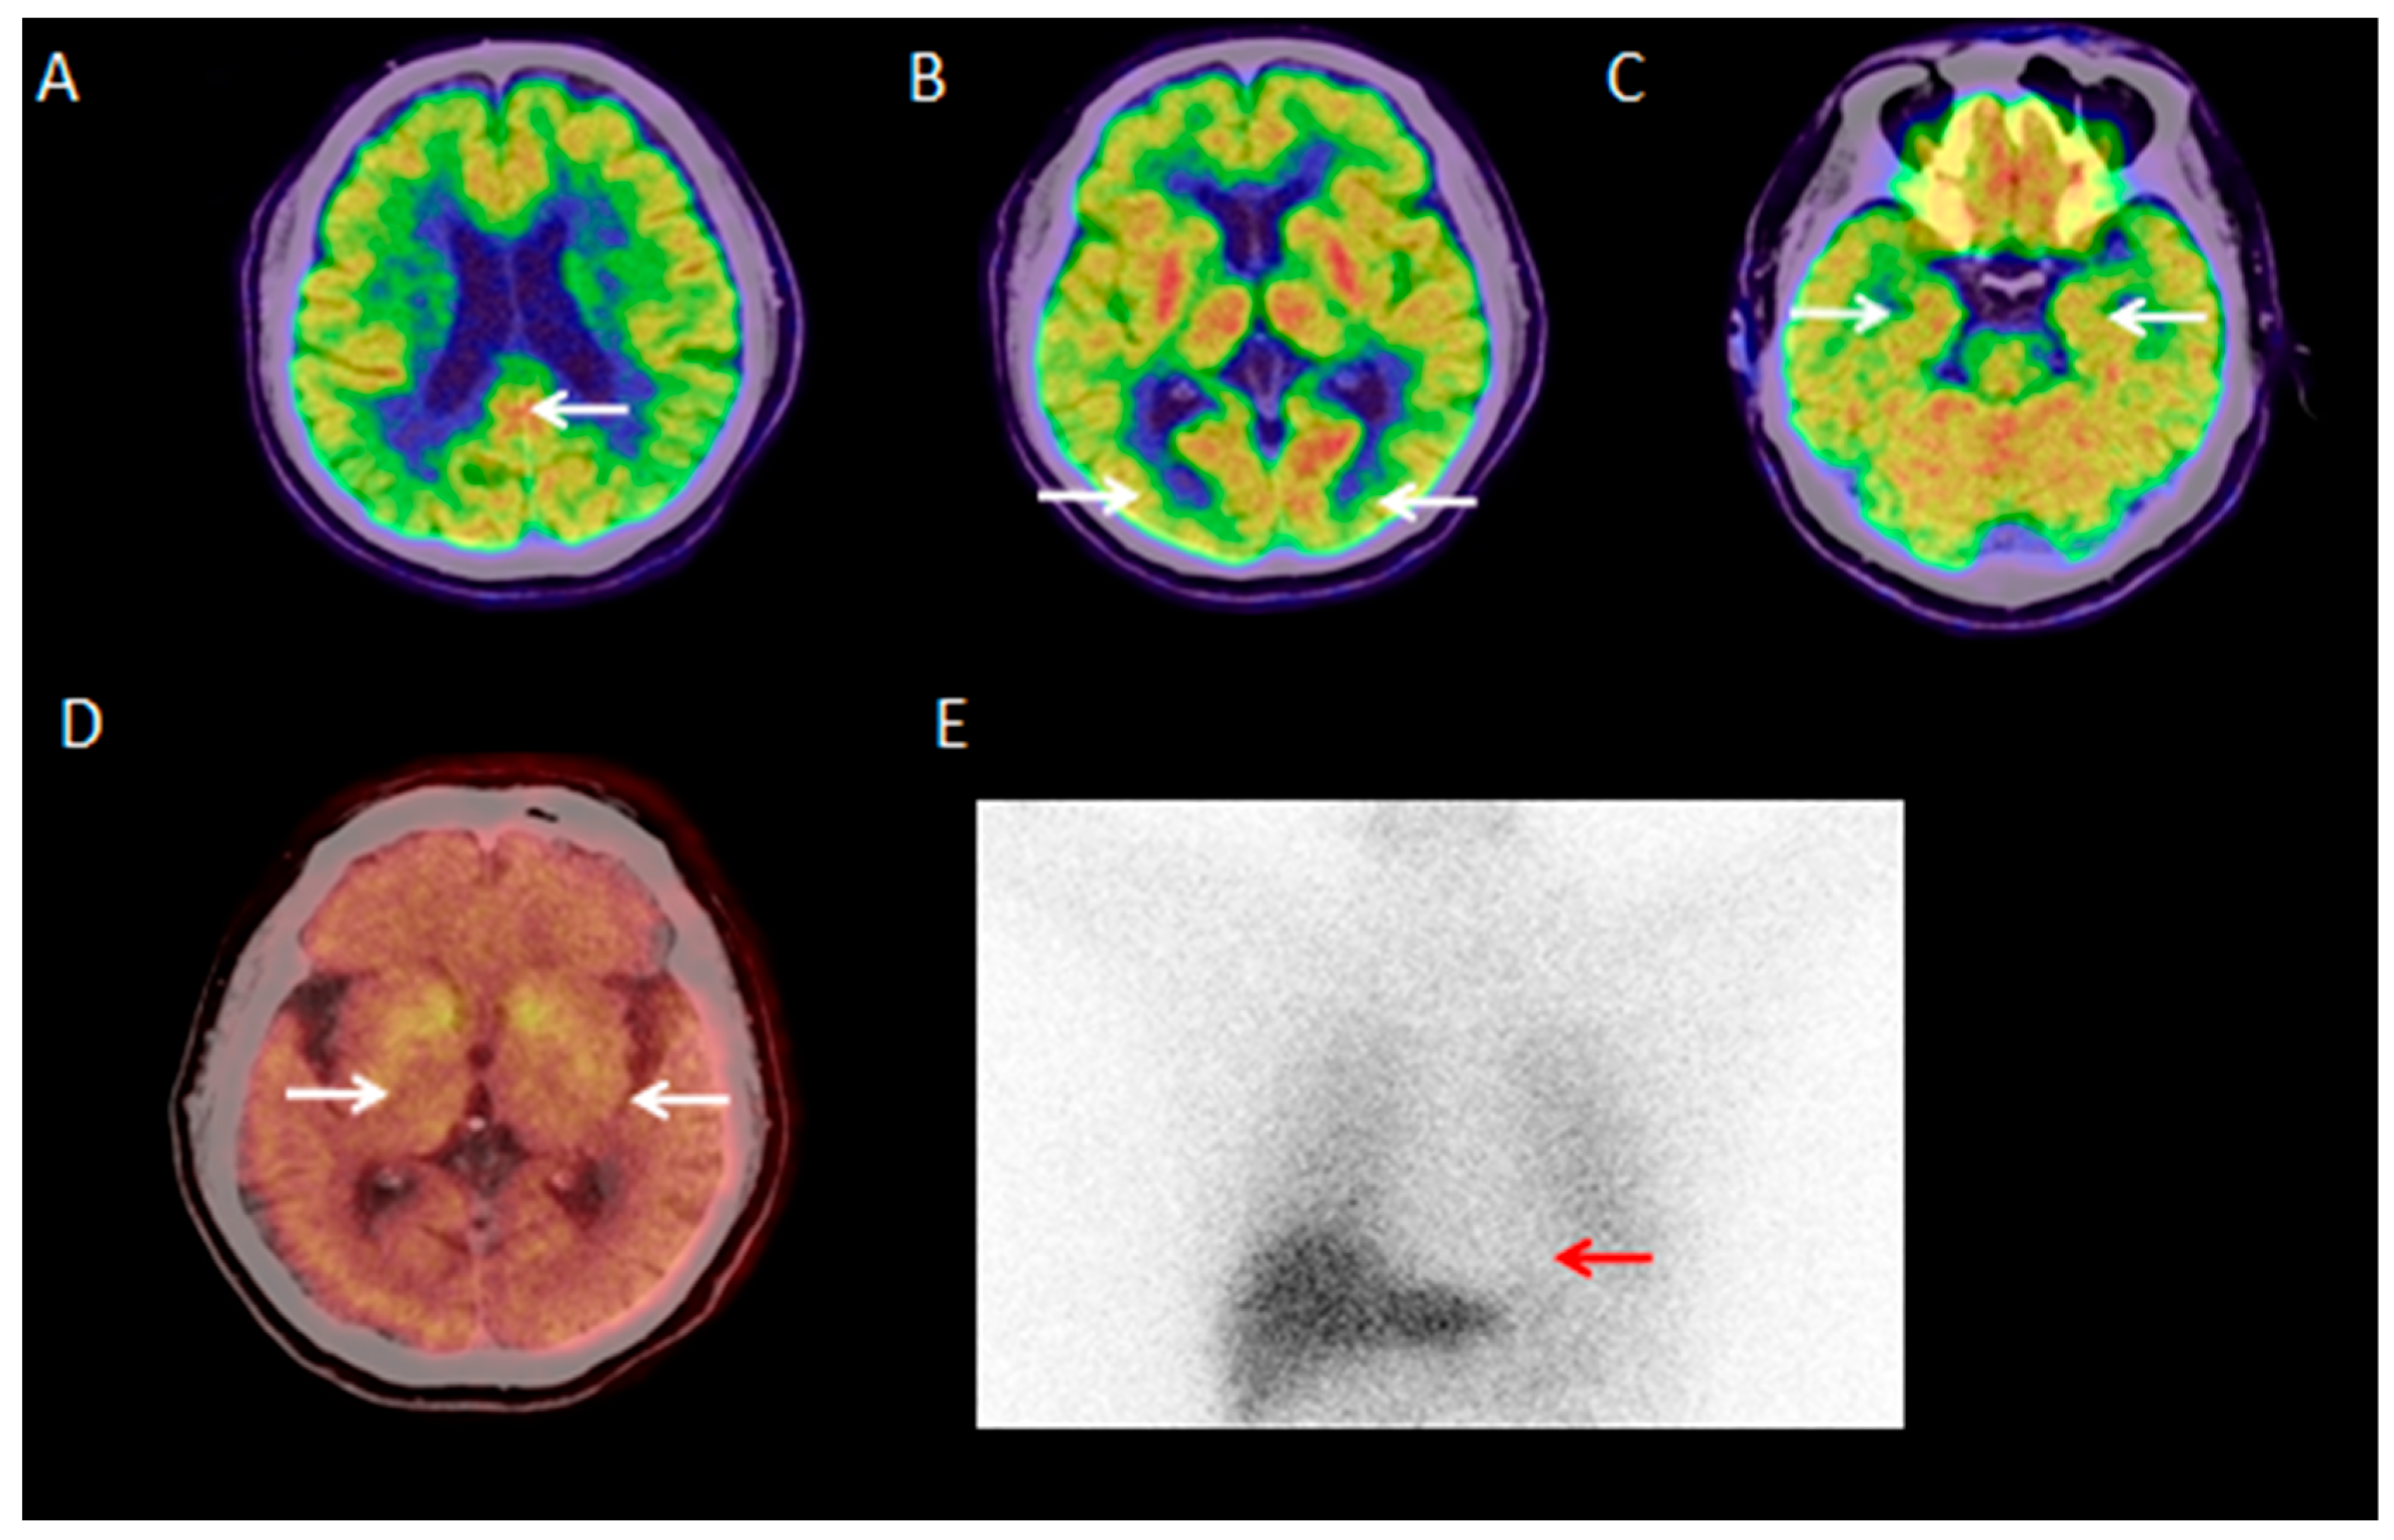

3.2.1. Visual Analysis of 18F-FDG PET/CT

3.2.6. Visual Analysis of 18F-FP-CIT PET/CT

3.2.7. Visual Analysis of 131I-MIBG SPECT

3.2.8. Visual Analysis of 18F-PM-PBB3 PET/CT